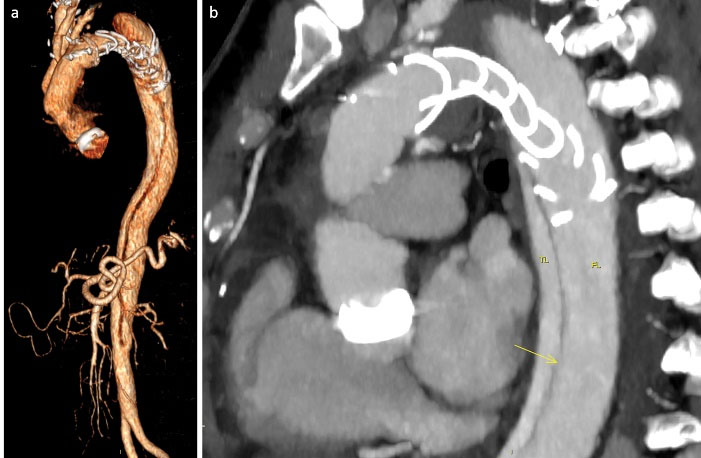

A 56-year-old male, previously operated with mechanical Bentall procedure and right coronary artery bypass grafting for acute type A aortic dissection, was admitted to our hospital with the diagnosis of residual type A chronic aortic dissection to undergo FET procedure. Total arch replacement with FET was performed in operative room (OR) using a 28/30 mm Thoraflex hybrid prosthesis (Vascutek, Inchinnan, UK). Briefly, after circulatory arrest and cerebral protection with selective bilateral antegrade cerebral perfusion at a target nasopharyngeal temperature of 25 °C, the hybrid prosthesis was deployed into the descending thoracic aorta. Distal anastomosis was performed at Ishimaru zone 2 of the aortic arch. Systemic perfusion was re-established through one of the side-branch of the hybrid prosthesis and then, the supra-aortic vessels re-implantation and the proximal anastomosis were completed. The post-operative period was uneventful although the pre-discharged computed tomography angiography (CT) scan control showed the incorrect deployment of the distal endovascular portion of the Thoraflex in the false lumen (). The residual flap length was about 25cm, extending from the middle tract of thoracic aorta to the sub-renal tract; celiac trunk, superior mesenteric artery and right renal artery originated from true lumen, left renal artery from false lumen. Then, the aortic team decided to perform an angiography to evaluate the feasibility to access the false lumen through an intimal tear visualized in the pre-discharged CT examination in the middle portion of the thoracic aorta (), in order to evaluate the possibility to create a communication between the stent graft portion of the Thoraflex in the false lumen and the true lumen. After the angiographic confirmation of the feasibility of the procedure, the patient was then scheduled to perform a thoracic endovascular aortic repair (TEVAR). In a hybrid operative room, with the support of intraoperative transesophageal echo-guidance, the access to the false lumen was through the cannulation of the intimal tear located in the middle tract of the thoracic aorta. Then, the cannulated tear was dilated with the use of balloon catheter (Medtronic Evercross Pta Baloon Catheter, 6x60mm and 8x60mm, Minneapolis, MN) (). After positioning of an ultra-stiff guide wire through the dilated tear, two stent grafts were released proximally (Gore Tag Thoracic Stent Graft 28 mm x 28 mm x 150 mm, Usa AZ) in the portion of the Thoraflex deployed into the false lumen and distally (Gore Tag Thoracic Stent Graft 31 mm x 31 mm x 150 mm, Usa AZ) in the true lumen of thoracic aorta above the celiac trunk (). The intraoperative angiography showed the successful outcome of the procedure (); the postoperative period was uneventful and the patient was discharged in seventh post-procedural day. The pre-discharged CT scan control confirmed the complete exclusion and thrombosis of the false lumen in the thoracic aorta (). The CT scan performed at two years follow-up confirmed the good result of the procedure ().

jcvtr-14-205-g001

Figure 1. CT scan control of FET shows the Thoraflex endoprosthesis in the false lumen (a) and the intimal tear (arrow, b) in the mid tract of descending thoracic aorta (TL = true lumen; FL = false lumen).